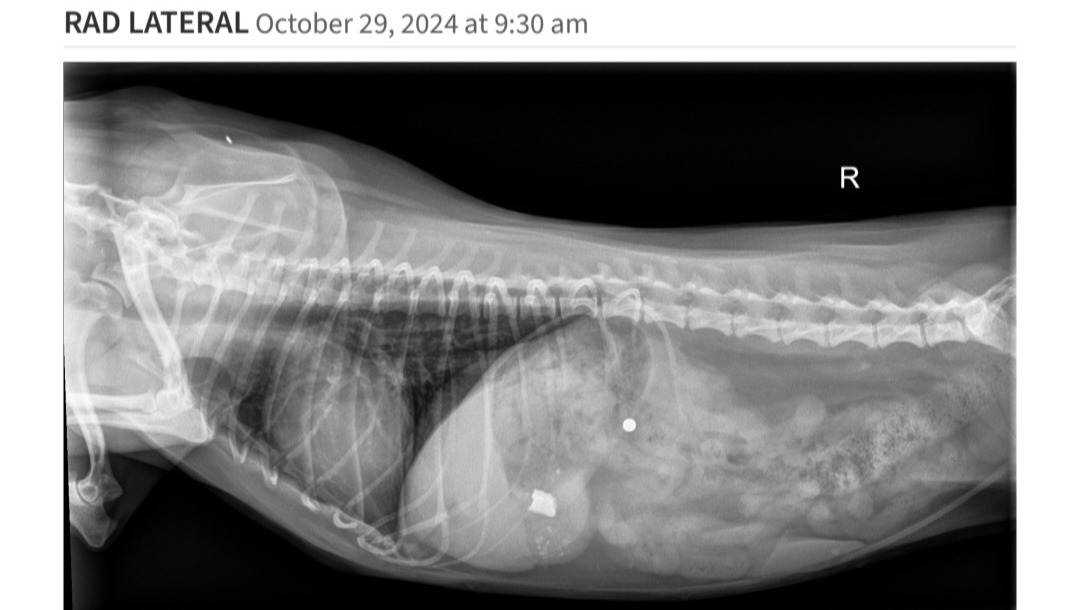

Little Freydis Potatis has been vomiting sporadically for a couple weeks, and we took her to the vet a few times to try and figure out why. When we took x rays on her most recent visit, we discovered that she swallowed an unknown object, and it's currently just vibing out in her stomach.